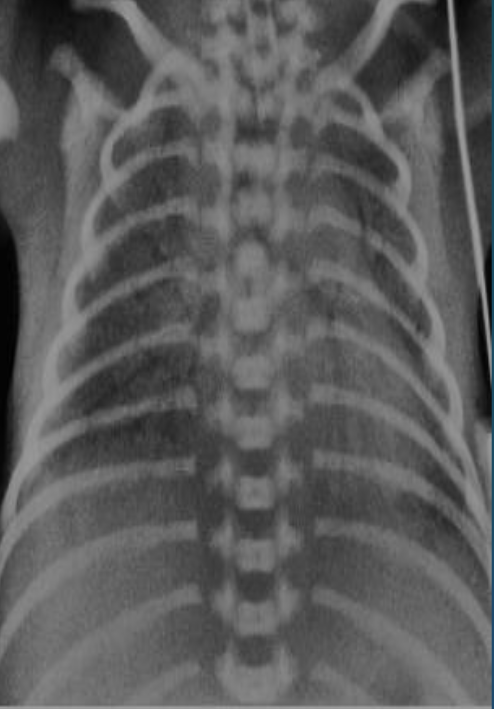

Imaging examination X-ray chest (frontal view) of a premature infant

Findings or description - General granular opacity of the lungs Note the uniformity of distribution of the changes in the lungs - The vessels, the heart borders and the diaphragm outlines are indistinct - Air bronchograms are visible.

Diagnosis Neonatal respiratory distress syndrome (hyaline membrane disease).